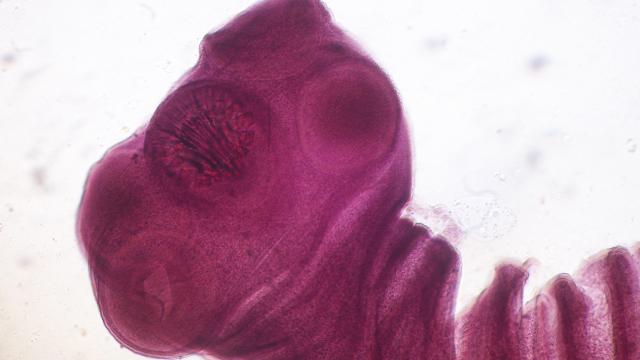

Microbiología y parasitología